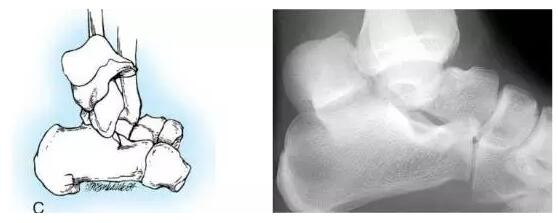

HawkinsⅢ型:距骨颈骨折移位伴胫距关节和距下关节脱位或半脱位